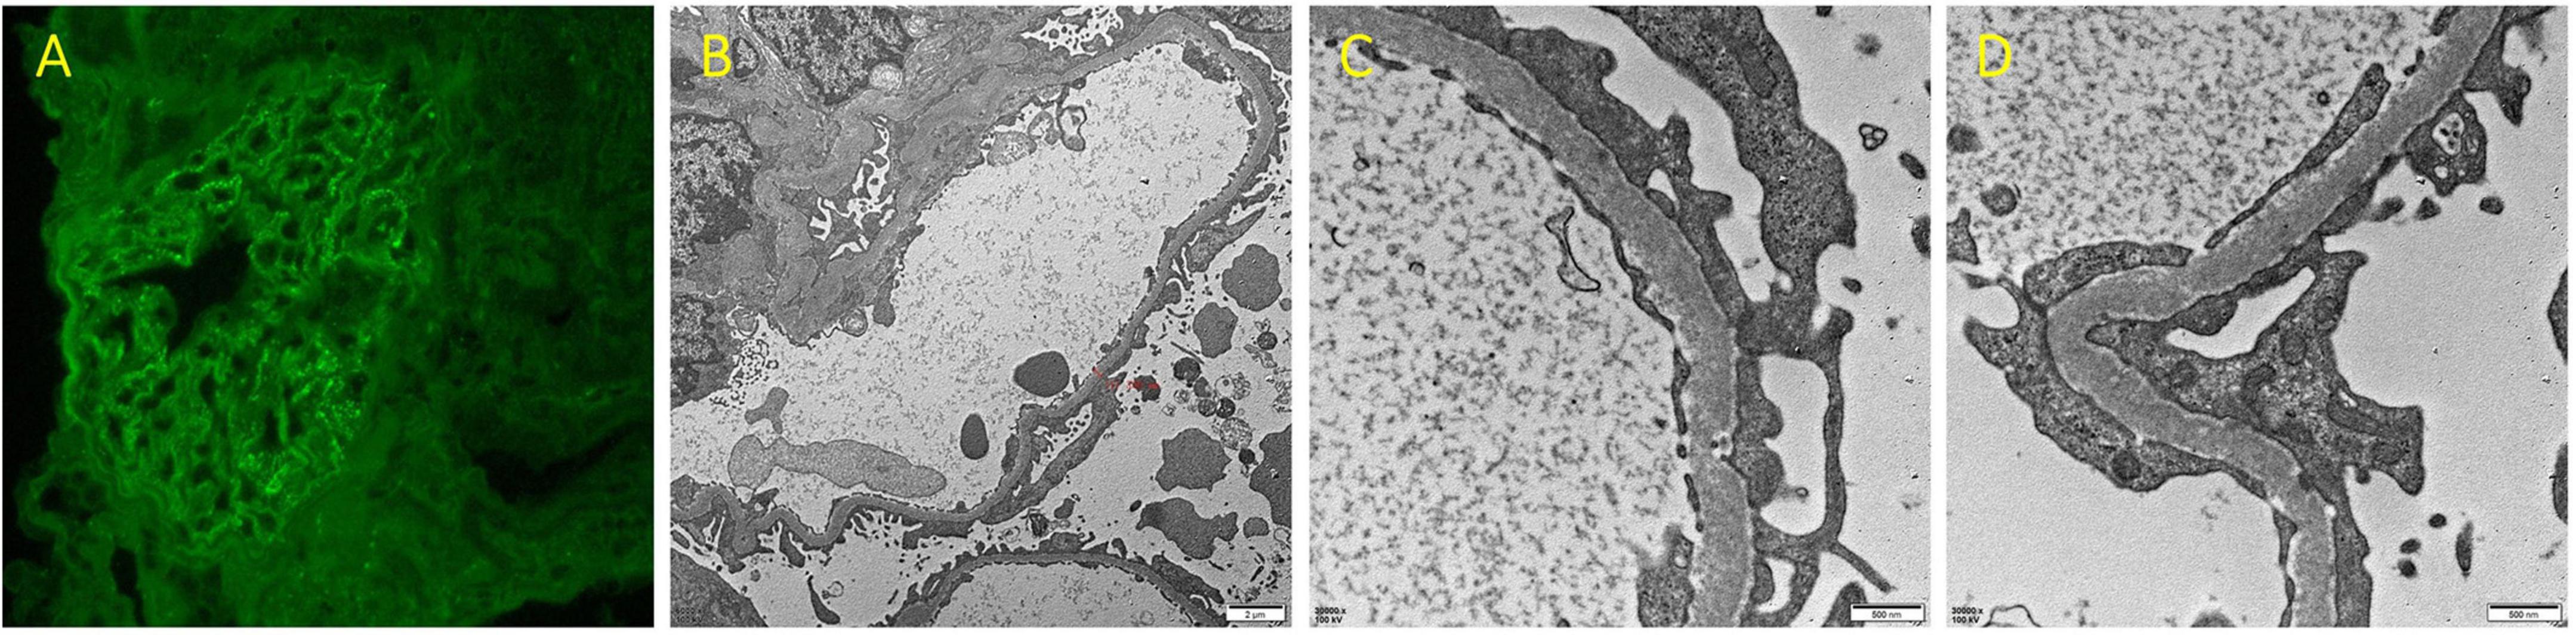

In view of NS, a renal biopsy was performed. Light microscopy revealed a stiff glomerular capillary loop, mild segmental proliferation of mesangial matrix and cells, and subepithelial fuchsinophilic deposits along the glomerular basement membrane (Figure 1). The immunofluorescence (IF) showed diffuse, granular IgG deposits in the glomerular capillary loop (Figure 2A). IF staining for PLA2R, thrombospondin type 1 domain containing 7A (THSD7A), and neural epidermal growth factor-like 1 protein (NELL-1) was negative. Electron microscopy demonstrated diffuse fusion (>80%) of podocyte foot processes, with small amounts of electron-dense deposits subepithelially (Figures 2B–D). These findings are consistent with membranous nephropathy (MN).

FIGURE 2

(A) Immunofluorescence staining for IgG of renal biopsy (×400). (B–D) Renal biopsy under electron microscopy (B ×6000; C,D ×30000).